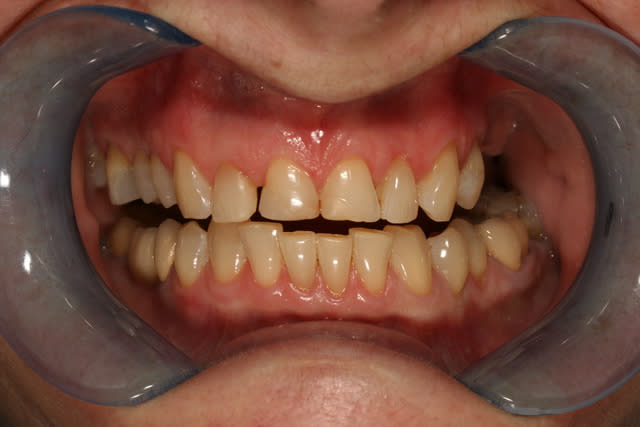

enfin un cas sympa pour faire des facettes, et a part une unitaire une fois c'est mon premier cas

le premier mock up était tout penché un peu plat, j'ai rajouté du composite par dessus la cire pour en faire un second qui nous plaise plus, à la patiente et à moi.

on a pas voulu toucher le collet de la 12, patiente pas motivée pour chir et ça me simplifiait la vie pour une première

ce sont des emax qui sont prévues

j'ai pris les empreintes, le rendez vous de pose est dans 2 semaines